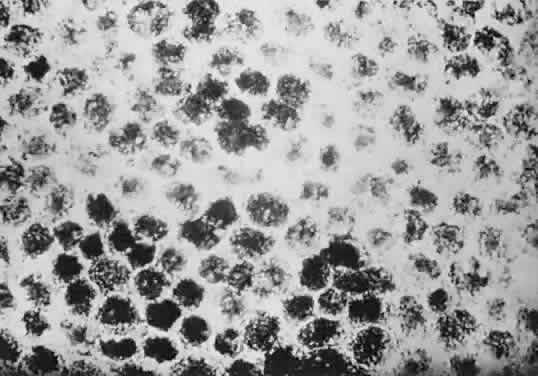

Histologically, congenital hypertrophy of the RPE is characterized by a monolayer of large RPE cells containing larger-than-normal pigment granules (Fig. 19; see Fig. 18B through E). Overlying photoreceptor elements have been shown to be degenerated, which explains the localized visual field defects corresponding to these areas.170

Fig. 19. A. Electron microscopic findings of normal-appearing retinal pigment epithelium (RPE) granules. B. Electron microscopy within area of congenital hypertrophy of the RPE shows enlarged pigment granules and a thickened basement membrane (bm) of the RPE cells. (Buettner H: Congenital hypertrophy of the retinal pigment epithelium. Am J Ophthalmol 79:177, 1975)